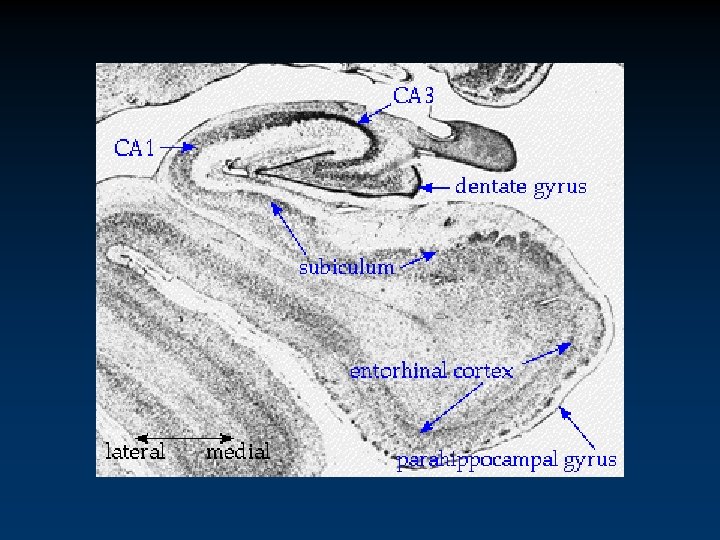

Integrated Circuitry Linking Temporal, Diencephalic, and Basal Forebrain Regions

CA 3 CA 1 DG subic